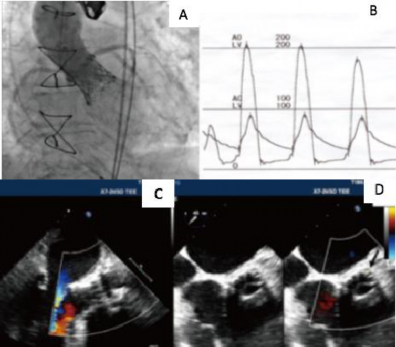

Năm 2019, Tada N và cs đã báo cáo trường hợp thay van ĐMC qua đường ống thông đầu tiên trên bệnh nhân sau mổ tái tạo van ĐMC bằng MNT tự thân theo phương pháp Ozaki. Đây là trường hợp bệnh nhân nam 80 tuổi, được phẫu thuật tái tạo van ĐMC bằng MNT tự thân theo phương pháp Ozaki cách 5 năm. Bệnh nhân được chẩn đoán hẹp van ĐMC đã tái tạo bằng MNT do lá van dài, dày và vôi hoá mép van (Hình 1.22). Bệnh nhân đã được tiến hành thành công thay van ĐMC qua đường ống thông (Hình1.23), kết quả

theo dòi sau 1 năm diện tích hiệu dụng của van 1,89 cm² và chênh áp trung bình qua van là 8 mmHg.69

Hình 1.23. Hình ảnh thay van động mạch chủ qua đường ống thông (A, B) và kết quả siêu âm tim (C, D) của bệnh nhân sau phẫu thuật tái tạo van động mạch chủ theo phương pháp Ozaki.69

“Nguồn: Tada 2019”.69